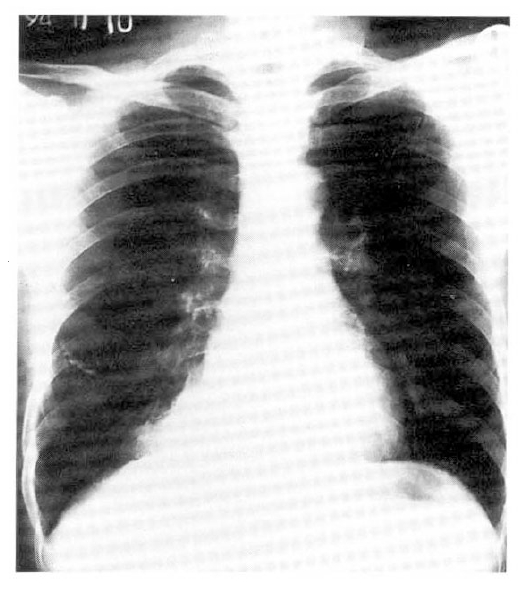

Fig. 1.

Conventional posteroanterior chest roentgenogram showing a well-defined mass in the posteromedial portion of the right lower lobe.

A 41-year-old male was admitted with fever, dry cough and pleuritic chest pain for 10 days. He had always considered his health to be good except that he had a subtotal gastrectomy due to peptic ulcer bleeding 20 years before admission. On examination, his blood pressure was 130/80 mmHg, pulse rate was 90/min and body temperature was 100.8 °F. Breathing sounds were diminished over the lower half of the right posterior chest. Laboratory data included a hemoglobin of 13g%, hematocrit of 44%, white blood count of 12,400/mm3 with 60% neutrophil, 35% lymphocyte, 4% monocyte and 1% eosinophil. IgE was 20 IU/ml. No pathogen was found in the smear and culture of the sputum. Immediate skin test to Aspergillus antigen was nonreactive. Serum precipitins to Aspergillus fumigatus were positive. Chest roentgenogram showed a well-defined mass in the posteromedial portion of the right lower lobe (Fig. 1). The pulmonary perfusion scan using 99mTc-macroaggregate albumin showed a perfusion defect in the right lower lung field, corresponding to the lesion in the chest roentgenogram. A computed tomographic scan of the chest showed a mass with soft tissue density in the posterior segment of the right lower lobe (Fig. 2). CT-guided biopsy specimens from the lesion showed aggregations of hyphae of Aspergillus.